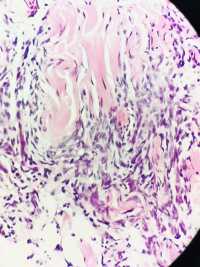

性别年龄32临床诊断

一般病史腹部肿物2年,术中见肿物紧邻皮下,与皮肤无黏连,肿物表面有粘液感,光滑

标本名称腹部肿物

大体所见灰粉结节一枚4*3.5*3cm,无包膜,切面灰粉实性质中,较细腻光滑

隆突,建议IHC标记排除腹壁纤维瘤病。

本例要鉴别的病种很多;建议:1.VIM;MUC4;SMA;SMA排除低度恶性纤维粘液样肉瘤;2,CD34排除“隆突”3.β-CATENINI,排除纤维瘤病;4.S-100,排除神经和脂肪来源;5。还需排除结节性筋膜炎的可能。

首先考虑隆突,建议做免疫组化协助与其他梭形细胞肿瘤相鉴别。

会诊结果:隆突。感谢各位老师!